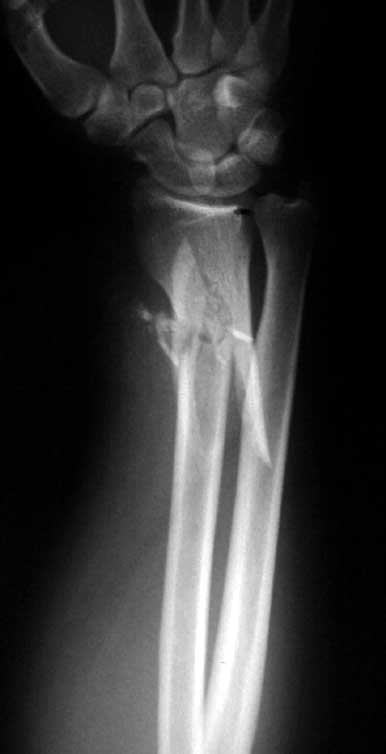

This patient is a 34 yo male raceboat driver who was ejected and had a propeller injury to his left non-dominant arm w/ amputation of digits 2-4 and dorsal wrist laceration and distal radius fracture w/ shaft extension.

We have seen a few of these injuries that are difficult to stabilize w/ standard implants due to the shaft extension. I recently received a Synthes proto-type from Dr. Daniel Rikli in Aurau, Switzerland of the standard T-plate w/long proximal extension. It is a good implant for these unusual injuries. I wanted to get opinions on what others would do w/ standard implants. The plate takes 3.5 mm screws proximally and 3.5 or 2.7 screws distally. In a closed injury I imagine I would use the plate volarly, but due to the dorsal wound and lack of extensor tendons we plated the fx dorsally. I think we all should encourage Synthes to make these plates widely available.